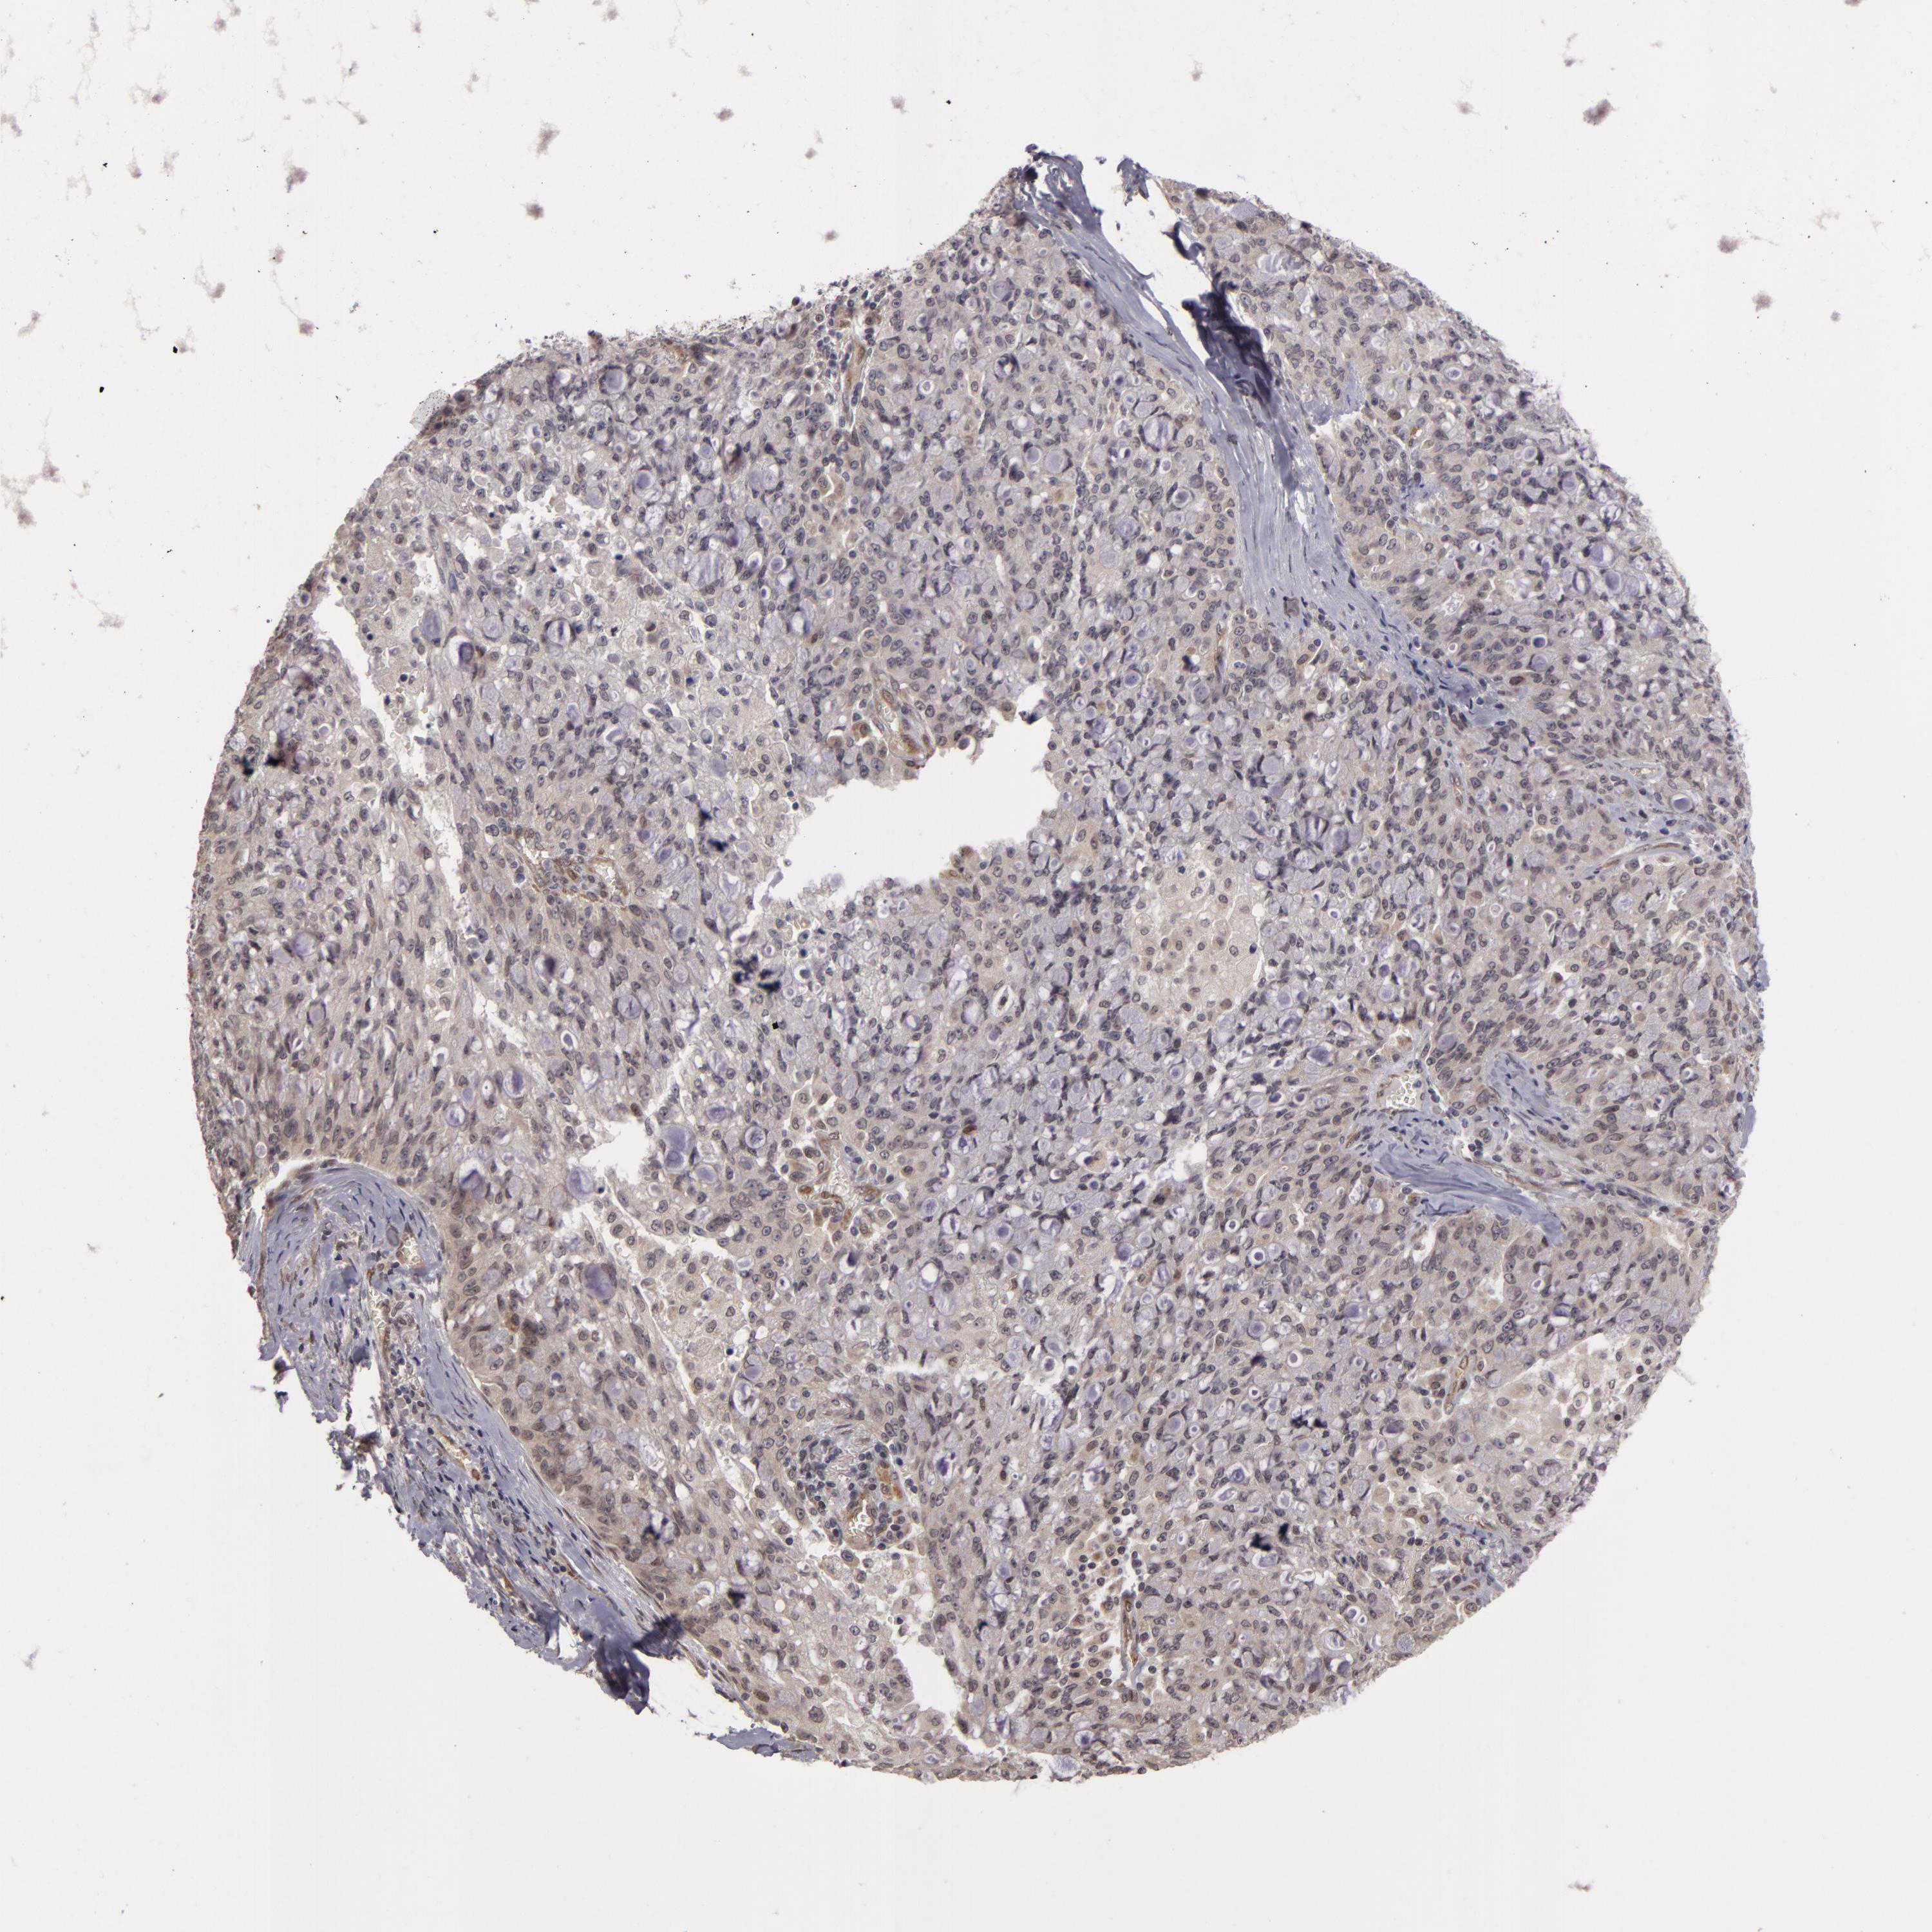

CANCER LUNG CANCER Show tissue menu

LUAD TCGA LUAD VALIDATION LUSC TCGA LUSC VALIDATION PROTEIN LUAD CPTAC PROTEIN LUSC CPTAC PROTEIN EXPRESSION

ANTIBODIES

AND

VALIDATION